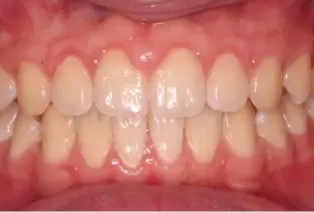

Intraoral photos